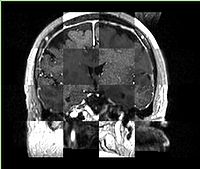

Checkerboard

Builds a "puzzle-piece" collage of blocks from both images, alternating between the two. Helpful if the two images are from different modality or have different contrast. Continuity of edges becomes very apparent on such images.

Case10-FLIRT-coronal.jpg